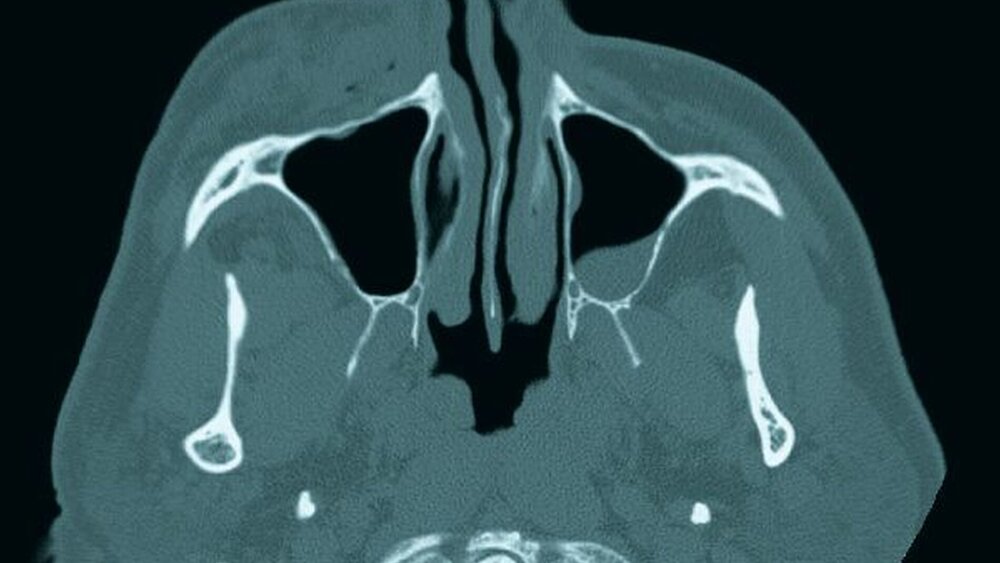

Eine 62-jährige Patientin im Zustand nach endodontischer Behandlung am Zahn 14 stellte sich bei uns in der Uniklinik vor. Bei der Spülung der Wurzelkanäle mit Natriumhypochlorit kam es zur Überpressung von Spülflüssigkeit in das periapikale Gewebe. Nach Abbruch der Behandlung bei einer eintretenden Schwellung im Bereich der Wange wurde die Patienten in die Klinik überwiesen.

Siehe Abbildung 10 bis 12.